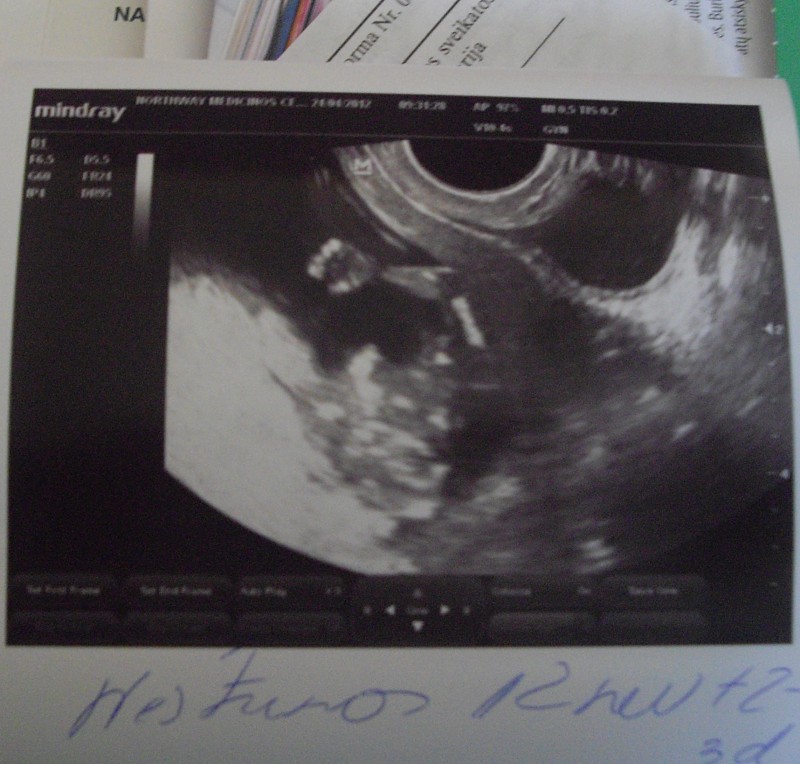

aš tai būčiau ir cd užsisakius, nes labai norėjau vyrui parodyti, nes jis buvo išvykęs į užsienį darbo reikalais ir negalėjo dalyvauti, o labai norėjo pamatyti leliuką, bet deja net nuotraukos negalėjo padaryti, nes leliukas miegojo rankelėm užsidengęs veiduką :D...lauksiu nuotraukos tavo džiaugsmelio![]()

ir uzsidenges veiduka, grazu, juk tai emocija, busena vaikelio, as buciau pasiemus ir tokia nuoltraukyte